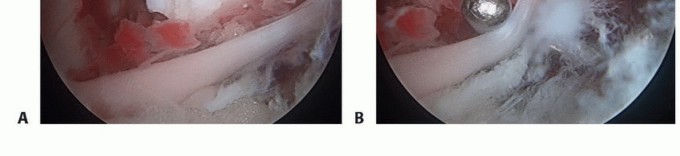

FIG 3 • Arthroscopic view of the knee. A. A completely displaced tibial spine fracture with interposition of the intermeniscal ligament blocks reduction of the fracture. B. Probe helps remove the entrapped intermeniscal ligament to allow proper reduction of the tibial spine fracture fragment.*

Attempt to reduce the fracture fragments as described earlier in the section “Fracture Reduction” (TECH FIG 1).

- TECH FIG 1 • A. Arthroscopic image taken of a type III tibial spine fracture. B. Arthroscopic image showing anatomic reduction of the fracture fragments.